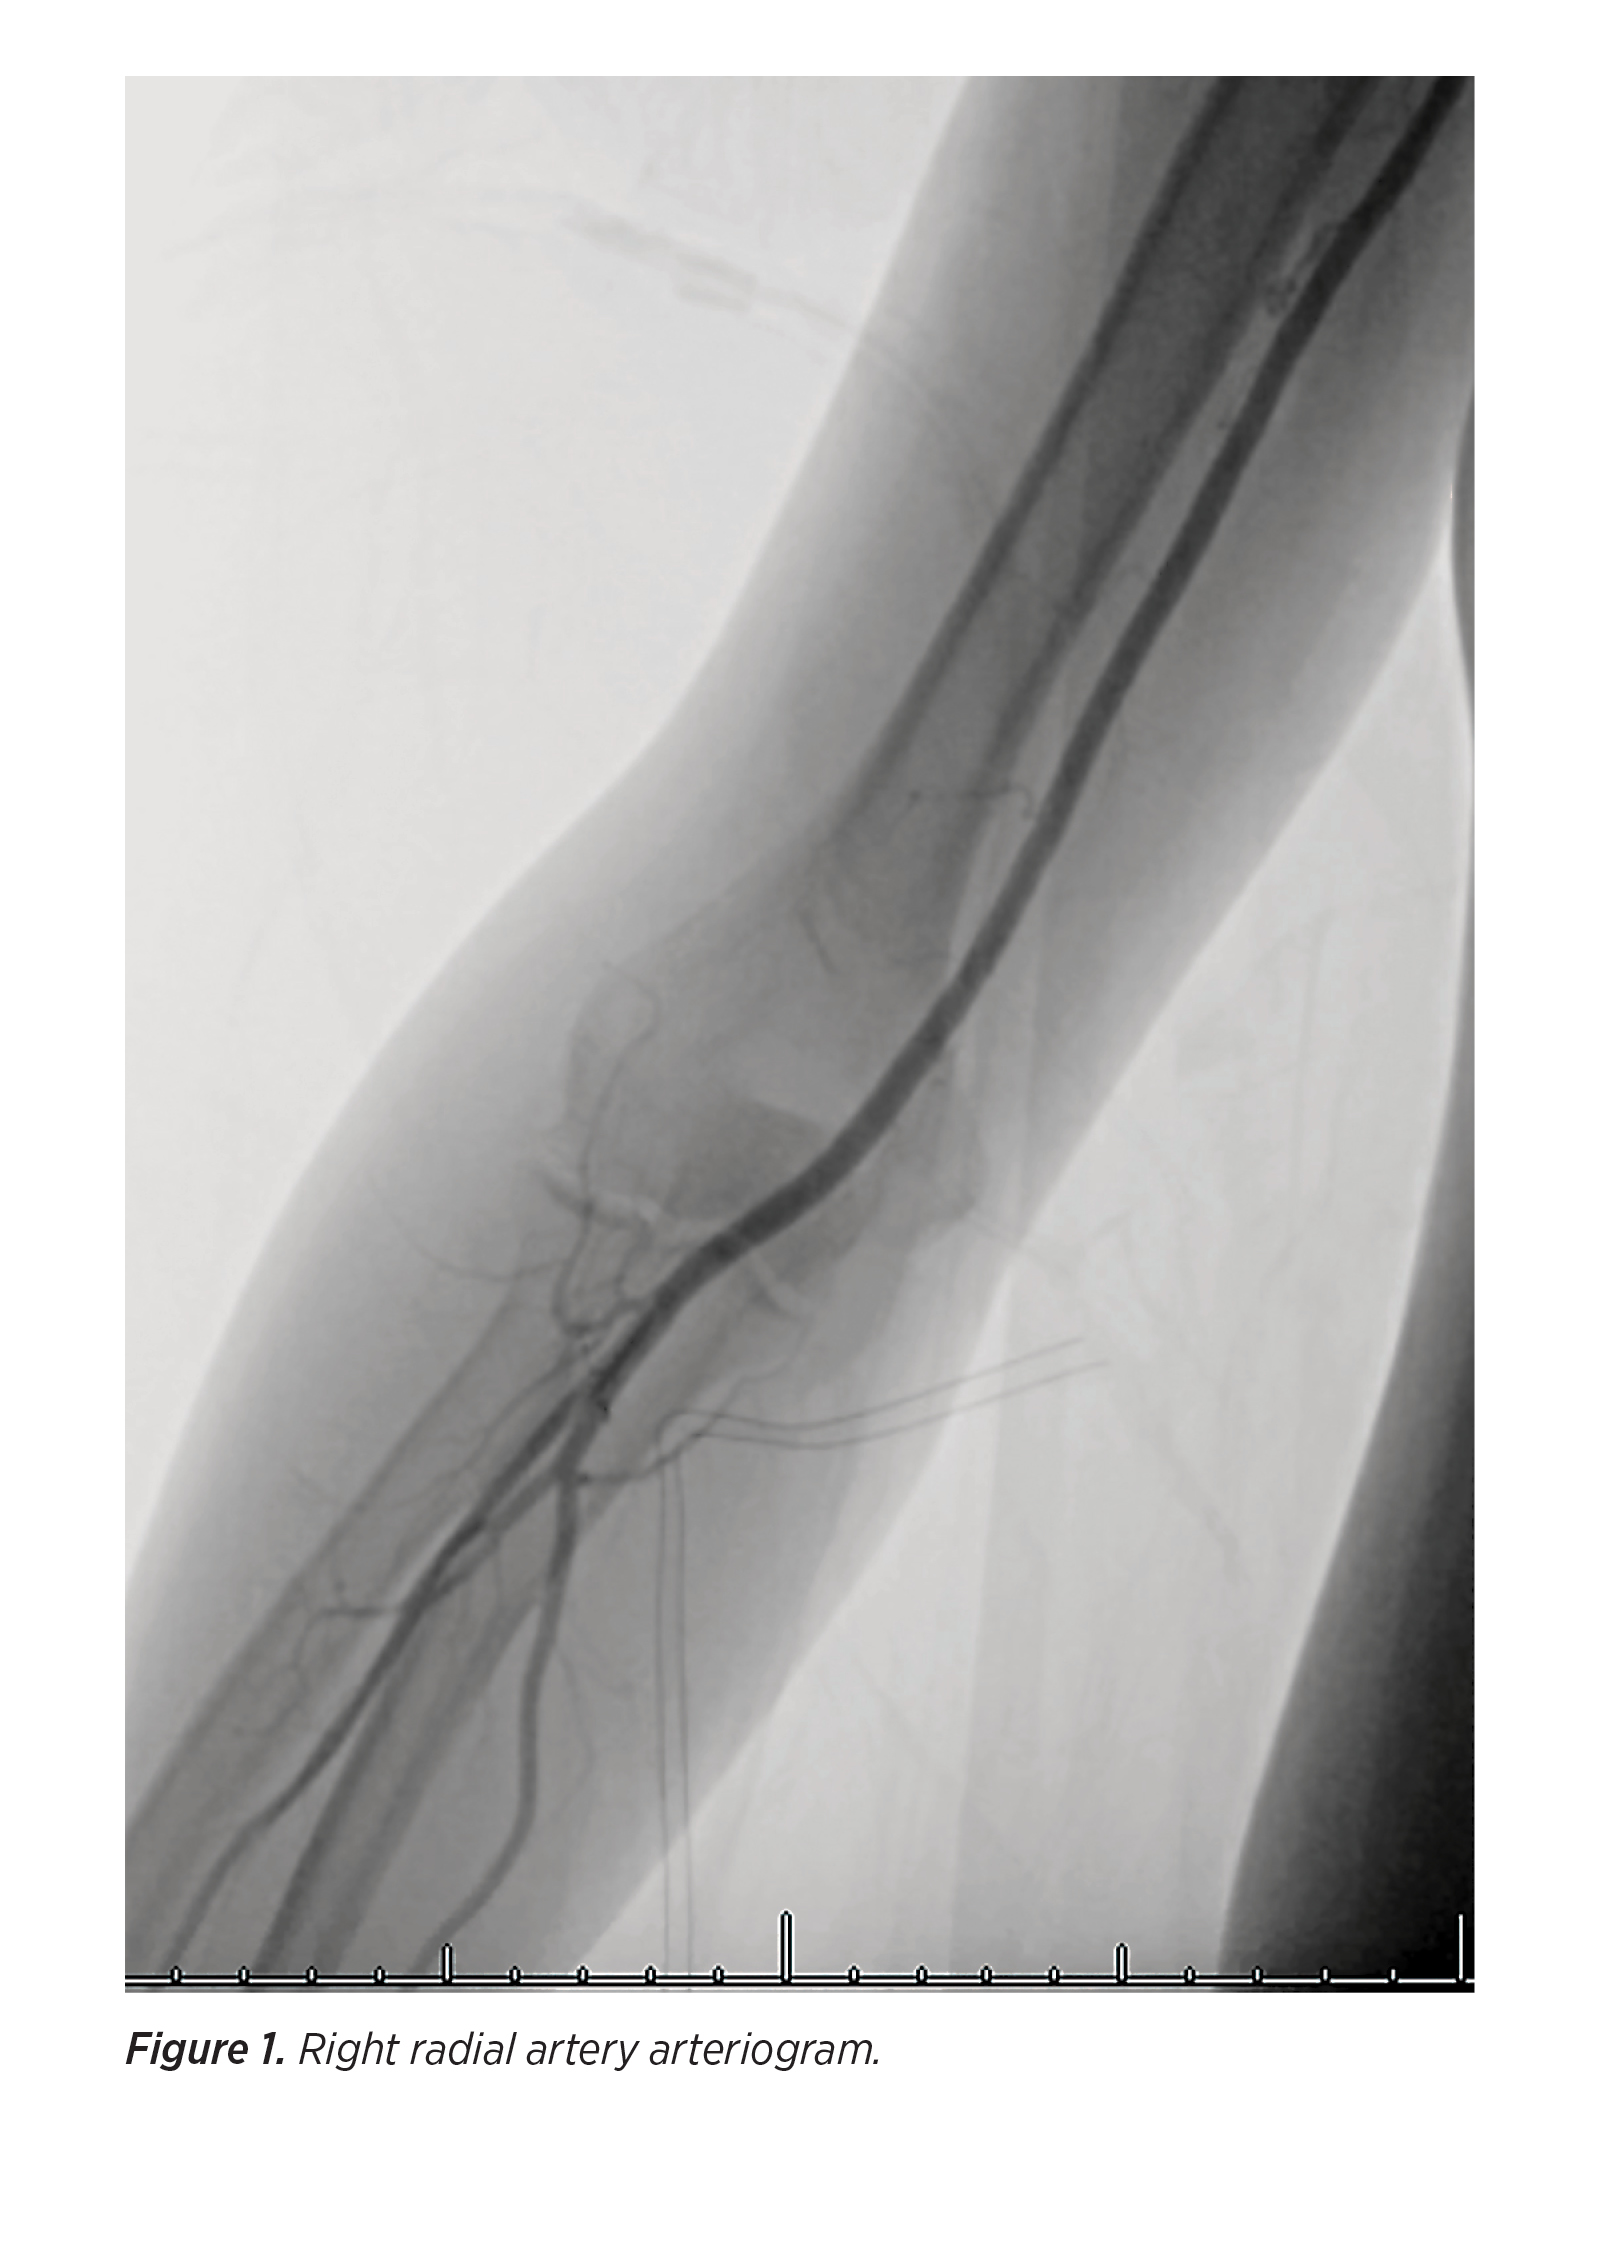

Radial Artery Access